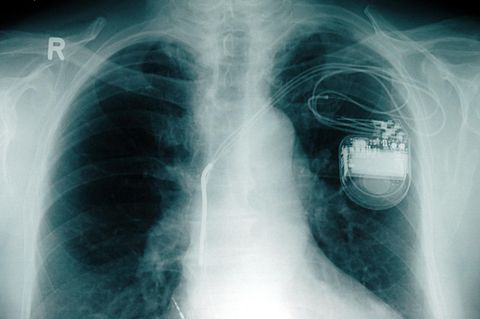

Auch problematische Zeiten lassen sich im Verband mit anderen leichter überstehen, etwa Hungerperioden, Stressphasen oder der Angriff von Schadstoffen. Genau diese Eigenschaft macht Biofilme zu einem Problem - und zwar immer dann, wenn sie sich innerhalb des menschlichen Körpers bilden, etwa im Innenohr, in den Harnwegen oder auf einem Implantat wie einem Herzschrittmacher oder einem künstlichen Hüftgelenk. Dann entstehen hartnäckige Infektionen, die schwer zu behandeln sind.